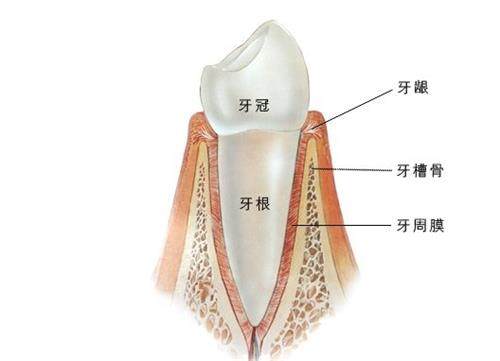

4. 牙周科:正规治疗牙龈炎、牙周炎等疾病